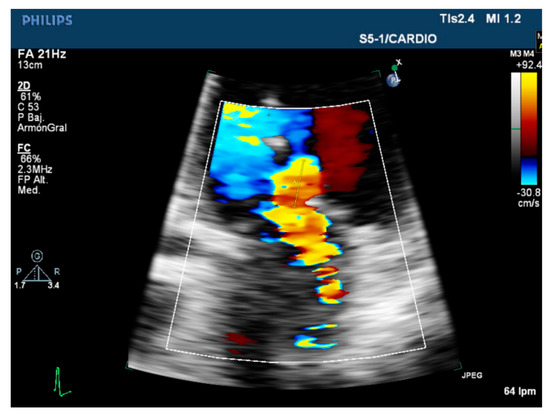

3.2. Semiquantitative and Qualitative Parameters

| Color flow jet | Qualitative. | Small, central. | Large central jet or eccentric reaching the posterior LA wall. |